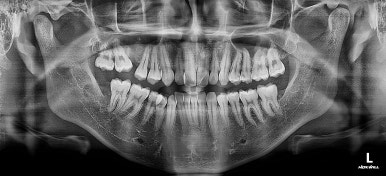

초진 시 X-ray 사진입니다.

위쪽 어금니 하나가 없는 걸 볼 수 있는데요.

다행히 해당 부위는 맨뒤에 사랑니까지 남아있던 상황이었어요. 환자분이 혹시나 하는 마음에 해당 부위 사랑니는 발치를 안하고 아껴두셨던거죠.